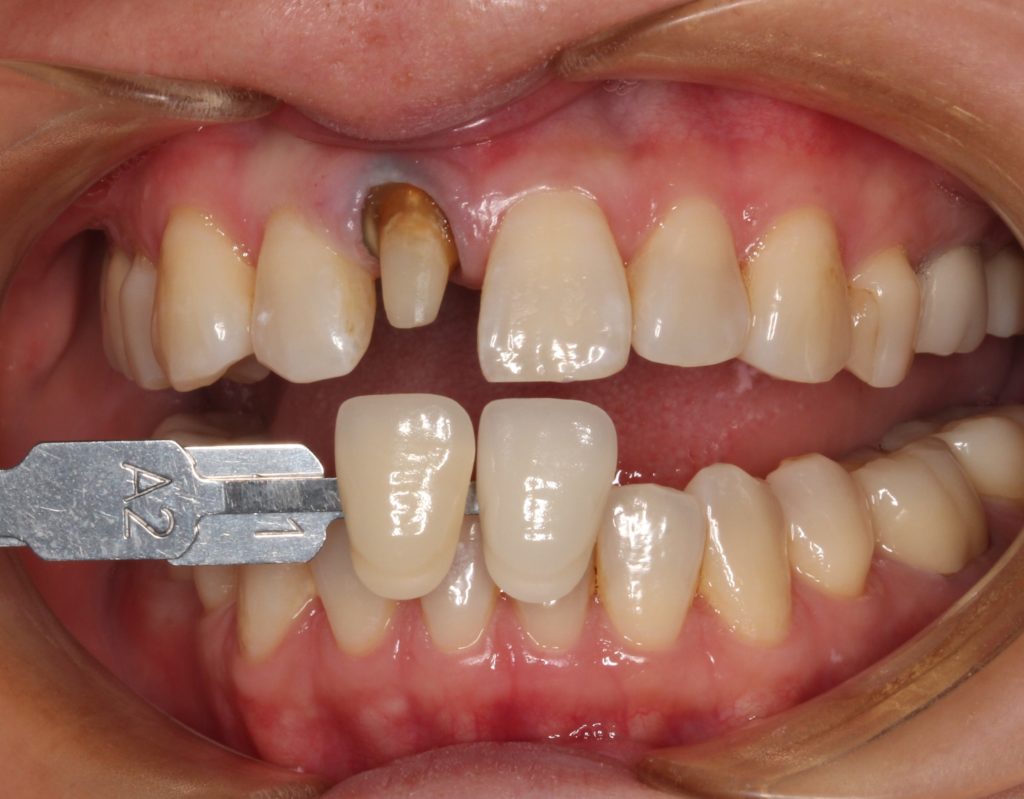

40代女性。「差し歯の入っている歯の根元が黒く、綺麗に治したい」という希望の方です。

早速、お口の中を見てみましょう。

矢印の歯ですが、根元が黒いのがすぐに分かります。

こちらの歯は若い頃に差し歯になってしまったようで。年々、根元のが目立ってきたようです。

歯の色見本を合わせ、周囲の歯の色を確認、記録します。